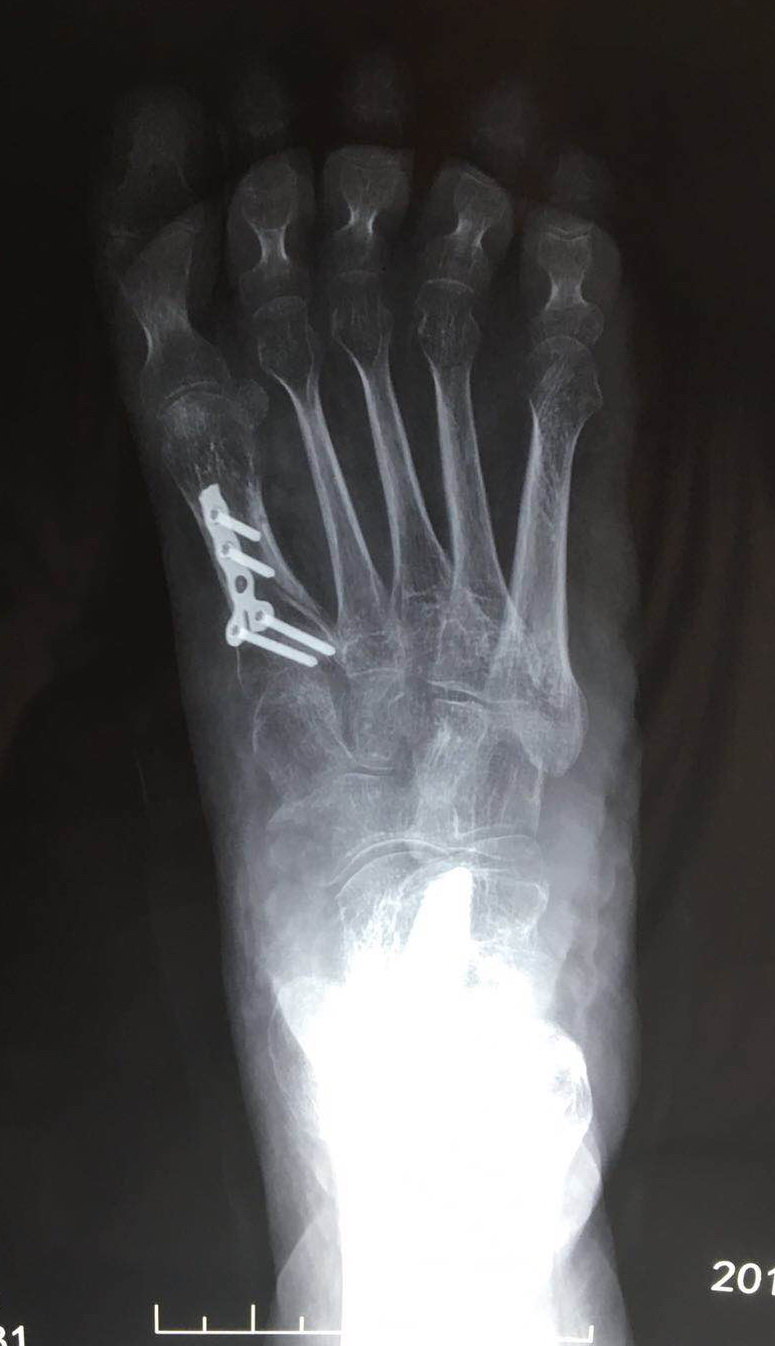

跖骨骨折,打了三块钢板!7月7号动的手术,现在已经月底了.

图片尺寸780x1052